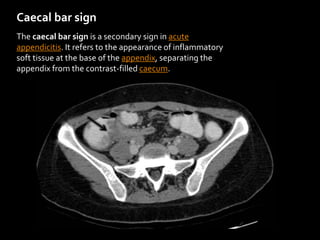

Caecal bar sign

The caecal bar sign is a secondary sign in acute

appendicitis. It refers to the appearance of inflammatory

soft tissue at the base of the appendix, separating the

appendix from the contrast-filled caecum.